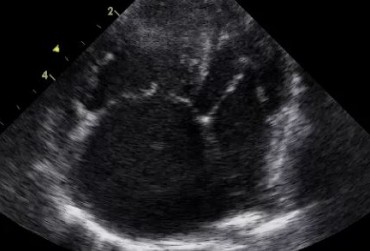

Obraz echo serca przez zabiegiem usunięcia worka osierdziowego 1

19 lutego 2019

Rafał Kraszewski